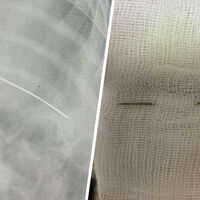

Хирурги Самарской областной больницы имени Середавина удалили швейную иглу, застрявшую в грудной клетке восьмимесячного младенца. Об этом сообщили в пресс-службе медицинского учреждения.

Родители показали дочку врачам, когда та начала сильно капризничать. Врачи на осмотре обратили внимание, что маленькая пациентка поджимает ногу, а также заметили подвисание руки. После этого младенца отправили на рентген ключицы и тазобедренного сустава. На одном из снимков медики увидели швейную иглу, вошедшую в грудную клетку ребенка. По мнению врачей, проткнувшая ребро насквозь игла и стала причиной ограниченной подвижности конечностей. После постановки диагноза ребенка прооперировали.

«Операция прошла успешно, и в настоящее время состояние девочки стабильное. Она чувствует себя хорошо и выписана домой», — рассказали в пресс-службе.

Детский хирург больницы Дмитрий Быков отметил, что, если бы игла вошла в тело на два сантиметра выше, она могла бы попасть в сердце ребенка.